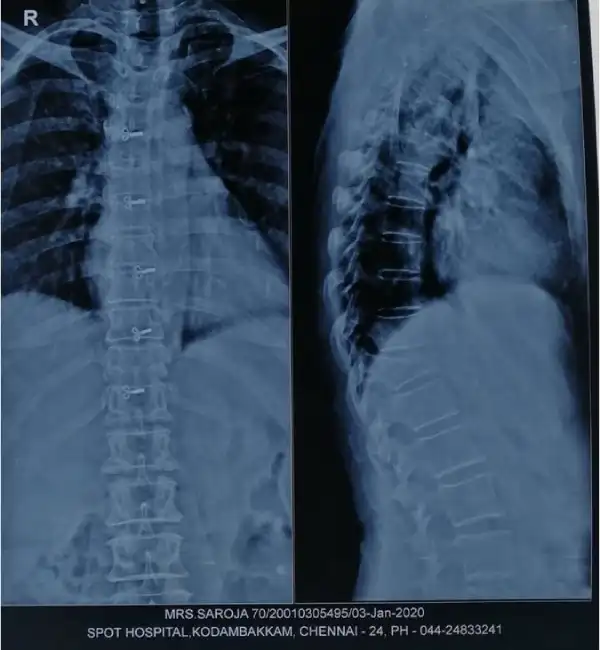

Pre Op X ray Vertebroplasty

Post Op X ray Vertebroplasty